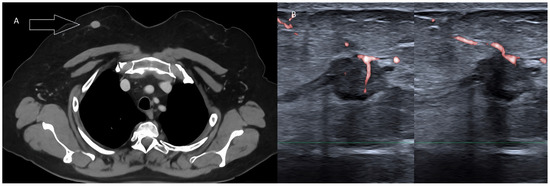

Figure 3. Invasive ductal carcinoma of the breast. (A) US scan showing a 4-mm nodule (calipers). (B) Extended FOV scan displaying the nodule (arrow) within the whole breast.

Figure 9. Ingrown areolar hair causing abscess formation in a young male. (A) Clinical photograph. (B) Power Doppler US imaging. The 6-mm linear echoic hair and the surrounding strong hyperemia are readily recognizable, allowing a confident differential diagnosis with Montgomery glands inflammation.